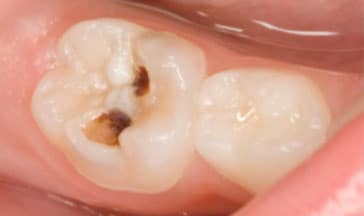

Smile Reveal #2

A perfect smile revealinvolving pulpotomies / stainless steel crowns

Before

Look how happy our patient looks after she received the services here at South Airdrie Smiles. We did buildups on her teeth and then recently provided pulpotomies / stainless steel crowns for the two teeth we built up. Her teeth were severely worn down. Now, she can’t seem to get enough of her gorgeous smile!